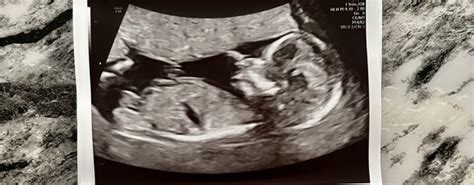

The 20-week scan , or anatomy scan, is a detailed ultrasound examination usually performed between 18 and 22 weeks of pregnancy. Its primary goal is to assess the baby’s physical development and screen for any structural abnormalities. During the scan, the sonographer will carefully examine various parts of the baby’s body, including the brain, heart, spine, limbs, and organs. They’ll also check the placenta and amniotic fluid levels. The scan provides crucial information about the baby’s health, allowing healthcare providers to plan for any necessary interventions or specialized care after birth.